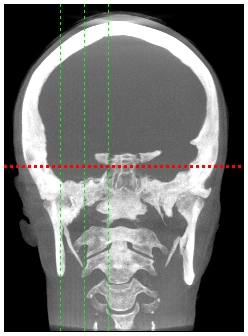

A 23-year-old girl presented to the Department of oral and maxillofacial radiology of the Lebanese University, with a chief symptom of pain in the right neck that worsened on turning the head. The dull, aching pain radiated to the right pre auricular and post auricular areas. The patient also reported intermittent dysphagia, nonspecific for certain food types. On physical examination, tenderness to palpation was elicited bilaterally in the tonsillar fossa region. She had a limited range of neck motion, especially rotation. Neck masses were neither palpable intra orally nor extra orally, and there was no cervical or submandibular lymphadenopathy. The remainder of the neck examination was normal, with a no palpable thyroid and a midline trachea. Radiographic evaluation consisted of a CBCT imaging modality that showed bilateral radiopaque bodies extending from the styloid processes lateral to the mandible (Figure 6,7).

Figure 6 3D reconstruction of the calcifications.

Figure7 MIP reconstruction of the calcifications.